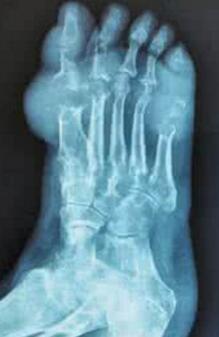

郑州市哪家医院可以切除痛风石